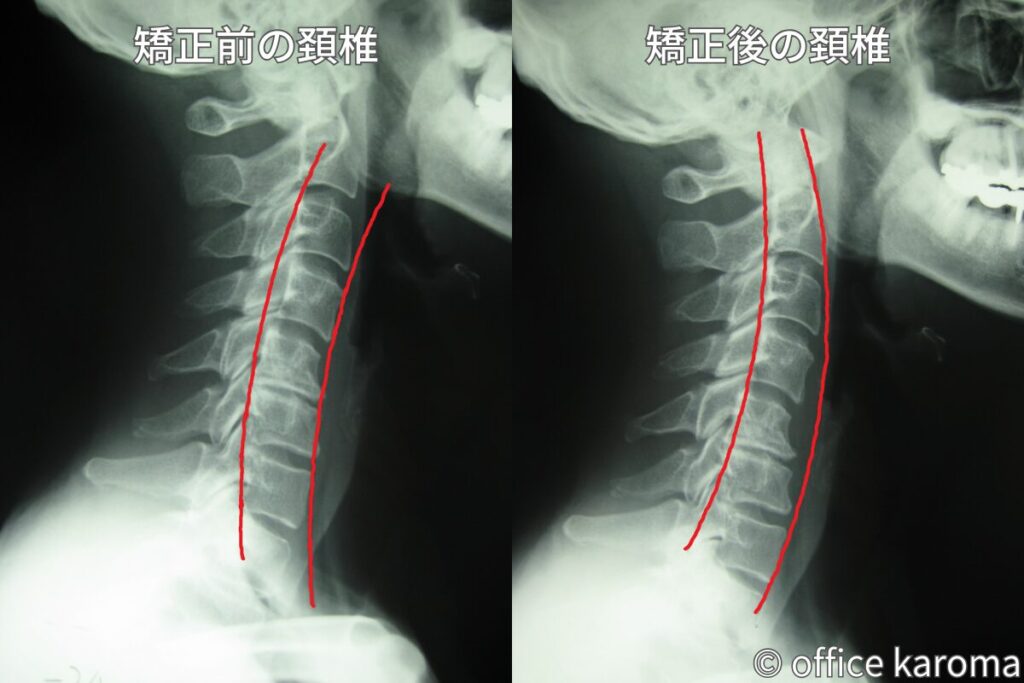

頚椎ヘルニアに関しては頚椎の歪みを矯正することで、飛び出した椎間板を元の位置に戻すことができます。

頚椎の歪みを矯正してカーブを元の形に戻せば、ヘルニアしている椎間板に掛かっていた圧力が下がるからです。

異常に高まっていた圧力が低下すれば陰圧の作用が働いて、押し出されていた椎間板が圧力の低い方へと移動していきます。

そうすれば、関節に過剰に掛かっていた負担も軽減されますし、脊髄や神経根の圧迫も解消されるので、首の痛みや腕の痛み・しびれも改善していきます。